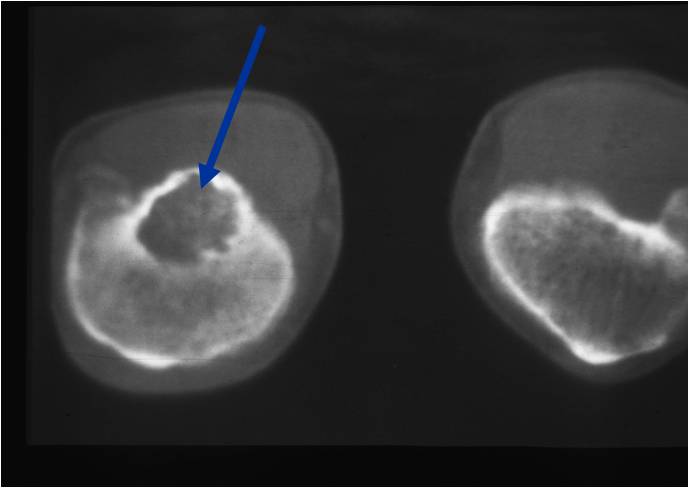

General Information Enchondroma is a benign indolent intramedullary hyaline cartilage neoplasm Accounts for 10% of all benign osseous tumors Limited growth, most lesions are less than 5 cm in maximal dimension Bones grow from a cartilaginous growth plate that...